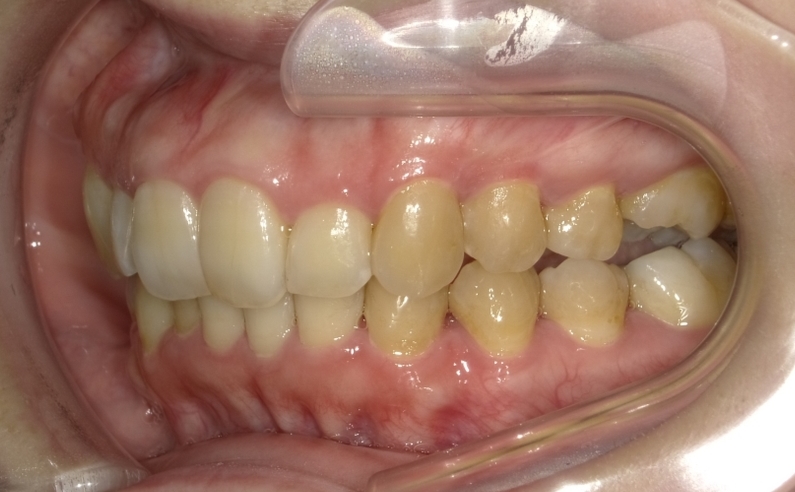

こちらがカウンセリング時のお写真です。

患者様のどこが気になっている部分か分かりますか?

抜歯は極力したくないという患者様で、スペースを取るために歯を多く削られてしまっています。

前歯を見るとよくわかりますよね?

↑左側で噛むことが出来ないという状態で、噛み合わせのズレが気になります。